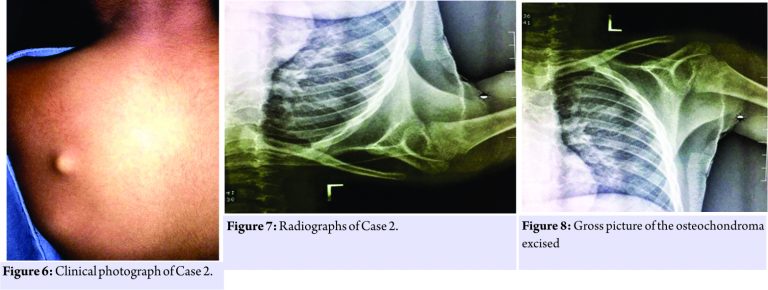

A 5-year-old male child presented to us with complaints of a swelling over the dorsal aspect of the left shoulder for birth. It was spontaneous in onset and gradually progressed to the present size. On examination, a hard, oval bony swelling of size 1.5 cm× 1cm was palpable on the dorsum of the left scapula along the medial border, non-tender, and fixed to the scapula and with normal pinchable overlying skin. There was no sensory or motor deficit in the left upper limb with a full range of motion of the left shoulder. There was no evidence of any other swelling in the body. Plain radiographs were inconclusive. CT scan of the left shoulder revealed a pedunculated osteochondroma arising from the dorsal aspect of the scapula.

The stalk was identified and the mass was excised in toto. The remnant stump was nibbled and dorsal surface of the scapula was smoothened using a file. The excised mass was sent for histopathological studies. A similar approach was used for both the patients. Histopathological studies both the patients confirmed the diagnosis of osteochondroma (Fig. 5, 6, 7, 8, 9).

Macroscopy showed bony fragment with soft tissue attachments of size 5 cm × 4 cm × 1 cm. Microscopy revealed multiple sections of bone fragments were seen with a cartilaginous cap with trabecular bone and fatty tissue. The cartilaginous cap was 3mm in thickness. The macroscopy of the second patient revealed single bony tissue fragment of size 1.5 cm× 1cm and microscopy showed bony trabeculae enclosing marrow spaces being capped by hyaline cartilage which was consistent with osteochondroma The patient was immobilized using an arm pouch. On the 3rd post-operative day, the patient developed a fever with multiple episodes of vomiting. His platelet count had dropped to 20,000/cumm and tested positive for dengue serology. His liver function tests were normal. The patient was transfused two units of platelet concentrate. He was kept nil oral with continuous fluid and electrolytes infusion. On the 6th post-operative day, the patient was symptomatically better. His operative wound was healthy. Platelets picked up to 52,000/cumm. Sutures were removed on the 10th post-operative day for both the patients. Pendulum exercises and shoulder strengthening exercises were initiated after suture removal. The patients were otherwise asymptomatic. The second patient post-operative period was uneventful. Sutures were removed on the 10th post-operative day.